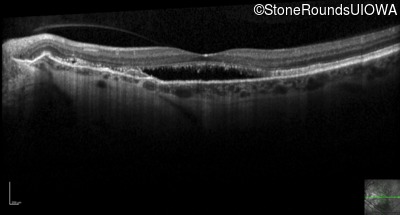

Optical Coherence Tomography - Left - 20/60 -1

Exemplar / OCT Stack